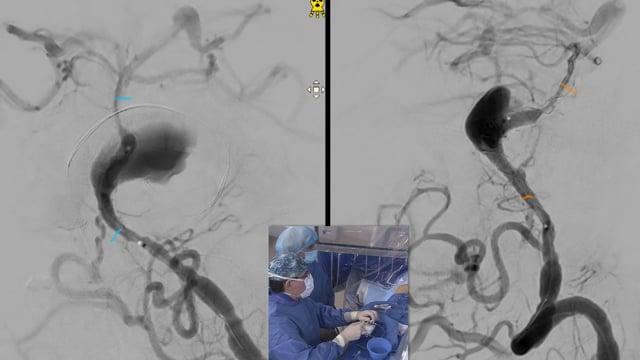

EVT For Ruptured PICA Aneurysm

AneurysmsStent assisted coiling

June 4, 2025